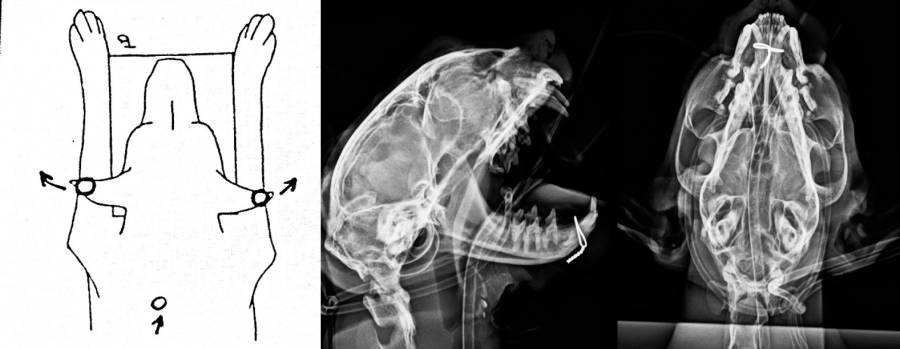

Röntgen Kopf

Röntgen Schulter